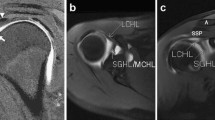

The CSA was calculated using the technique described by Moor et al. [16]. On the AP radiograph, the angle between the glenoid and the lateral border of the acromion was measured (Fig. 1). For the MRIs, the measurements were taken using the coronal–oblique T1 or proton density-weighted image. The MRI slice which depicts the most lateral acromion border was selected. The lateral border of the acromion was marked with the cursor (Fig. 2a). Next, the MRI slice which runs through the centre of glenoid was selected, and the measurement was completed (Fig. 2b). CSA measurements were taken to one decimal place and were taken between April and May 2013 using Stryker OfficePACS Power 4.1 Express Edition (Kalamazoo, MI).

Coronal–oblique proton density-weighted fat-suppressed MRI image of the shoulder showing the CSA defined by MRI. Frequently, the most lateral extent of the acromion is located dorsally of the central glenoid plane. Therefore, the slice presenting the most lateral extent of the acromion is determined and marked with the cursor (a). After scrolling to the plane that includes the acromion centre, the critical shoulder angle is measured (b)